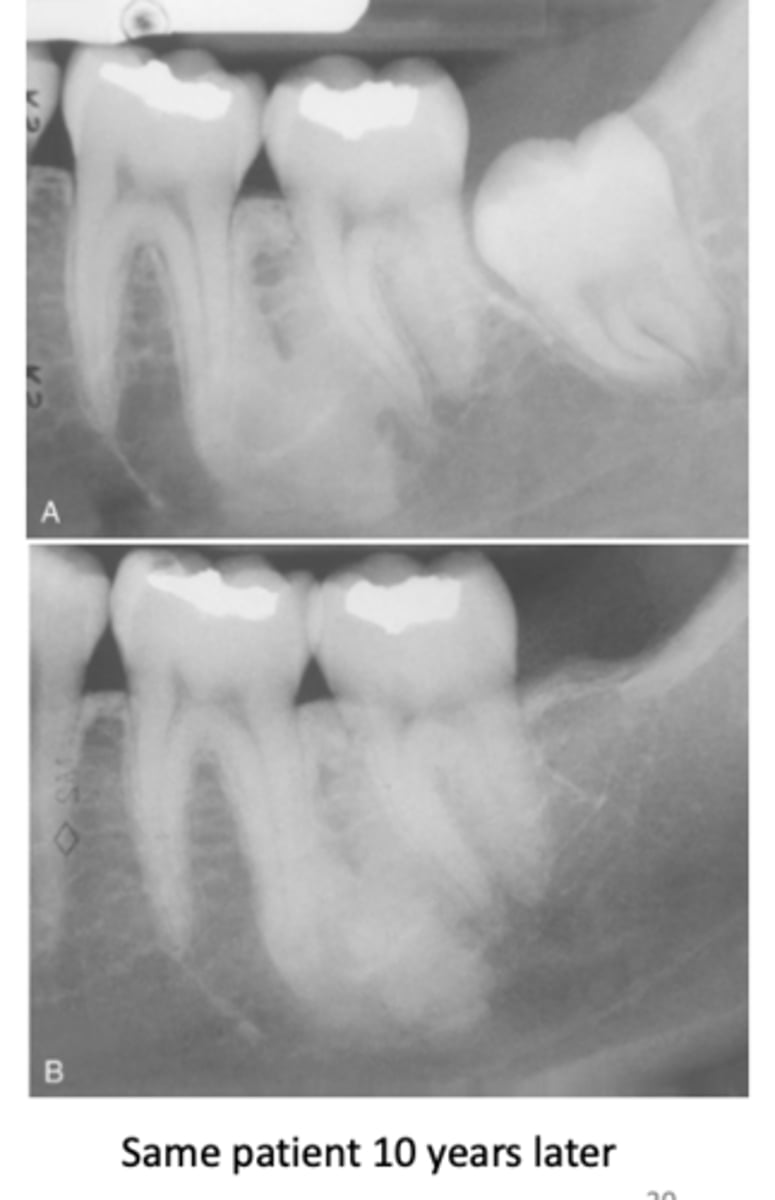

What do radiographic signs show in Idiopathic Osteosclerosis

Well-defined radiopacity

Most are associated to a root apex

What is the treatment for Idiopathic Osteosclerosis

Follow-up with radiographs if discovered during adolescence